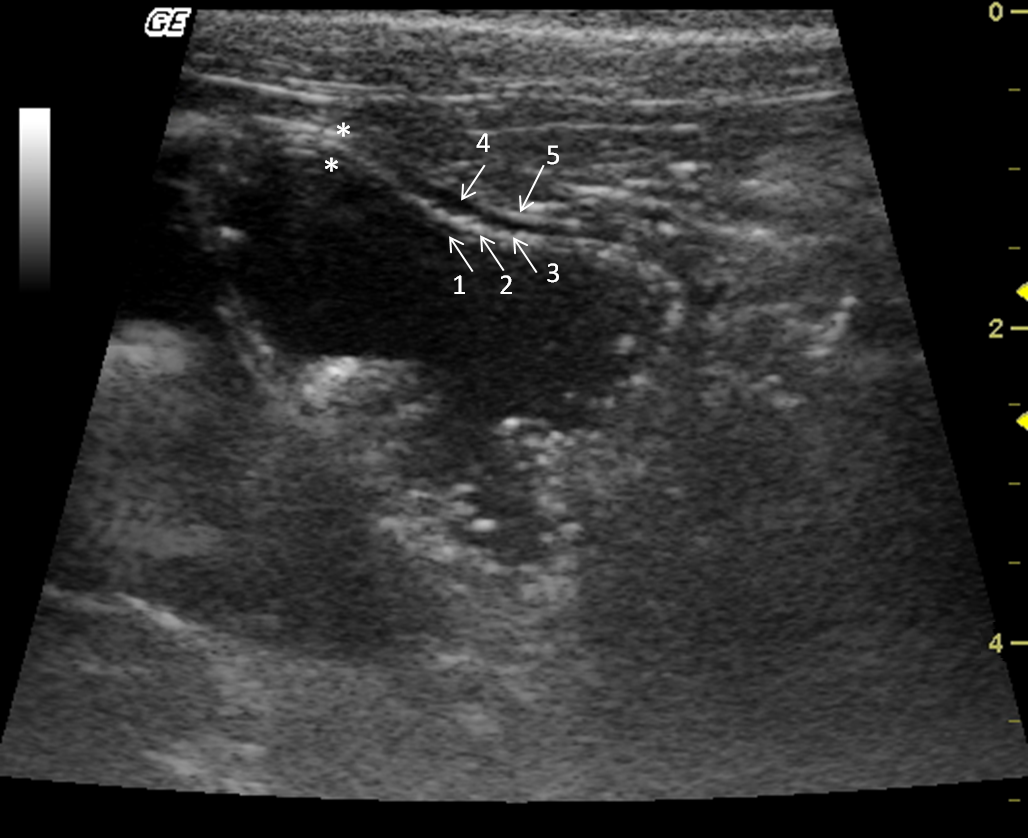

The stomach was observed caudal to the liver. Mild peristaltic activity was present, but it could not be quantitatively assessed because the animals were under anaesthesia. The stomach was distended by gas, and in spite of fasting, there was mild to moderate amount of anechoic content with hyperechogenic sediments, indicating the presence of water and food remnants. The average wall thickness was 2.8 mm. There were four layers alternating between hyperechogenic and hypoechogenic (Fig. 6). Stomach wall layering was detected in all individuals, the gastric mucosa and muscularis layers were anechoic, whereas the sub-mucosa and serosa were hyperechoic. During post-mortem examination the gastrointestinal tract structures were identified (Fig. 7).

The howler monkey is considered an endangered species in Brazilian territory mostly due to habitat destruction and illegal hunting (Bicca et al. 2006). Information regarding the abdominal sonographic anatomy of the howler monkey has not been reported. It is rare to find howler monkeys in research facilities (Costa et al. 2005; Gregorin 2006; Mendes et al. 2003). The small number of individuals that were submitted to sonographic examination is one limitation of this study. Another limitation was anaesthesia time, as the monkeys were sedated for their annual checkup; time was limited for obtaining ultrasound parameters of other organs. Further studies are needed in order for obtaining more parameters Figs 6, 7.

|

Figure 6. Transverse sonogram of the Alouatta fusca stomach. This structure is filled with anecoic (liquid) and hyperechogenic dots (food remains). The gastric wall has alternated echogenic pattern (arrows) (1) lumen; (2) mucosa; (3) submucosa; (4) muscularis; (5) serosa. |